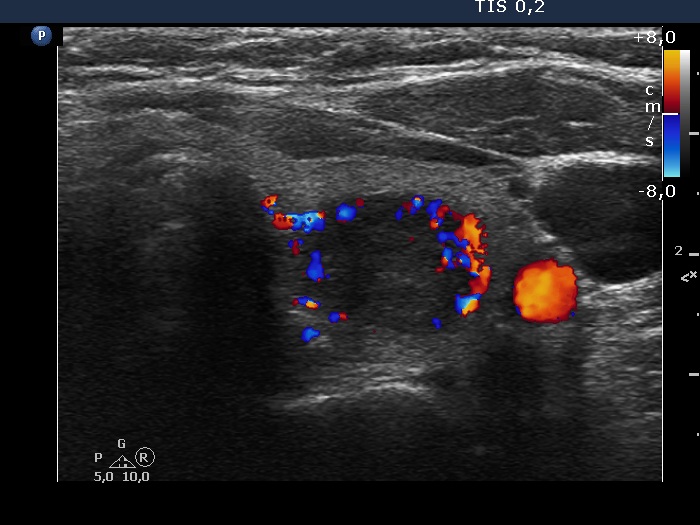

Left lobe, transverse scan, color Doppler mode. The nodule has perinodular blood flow.